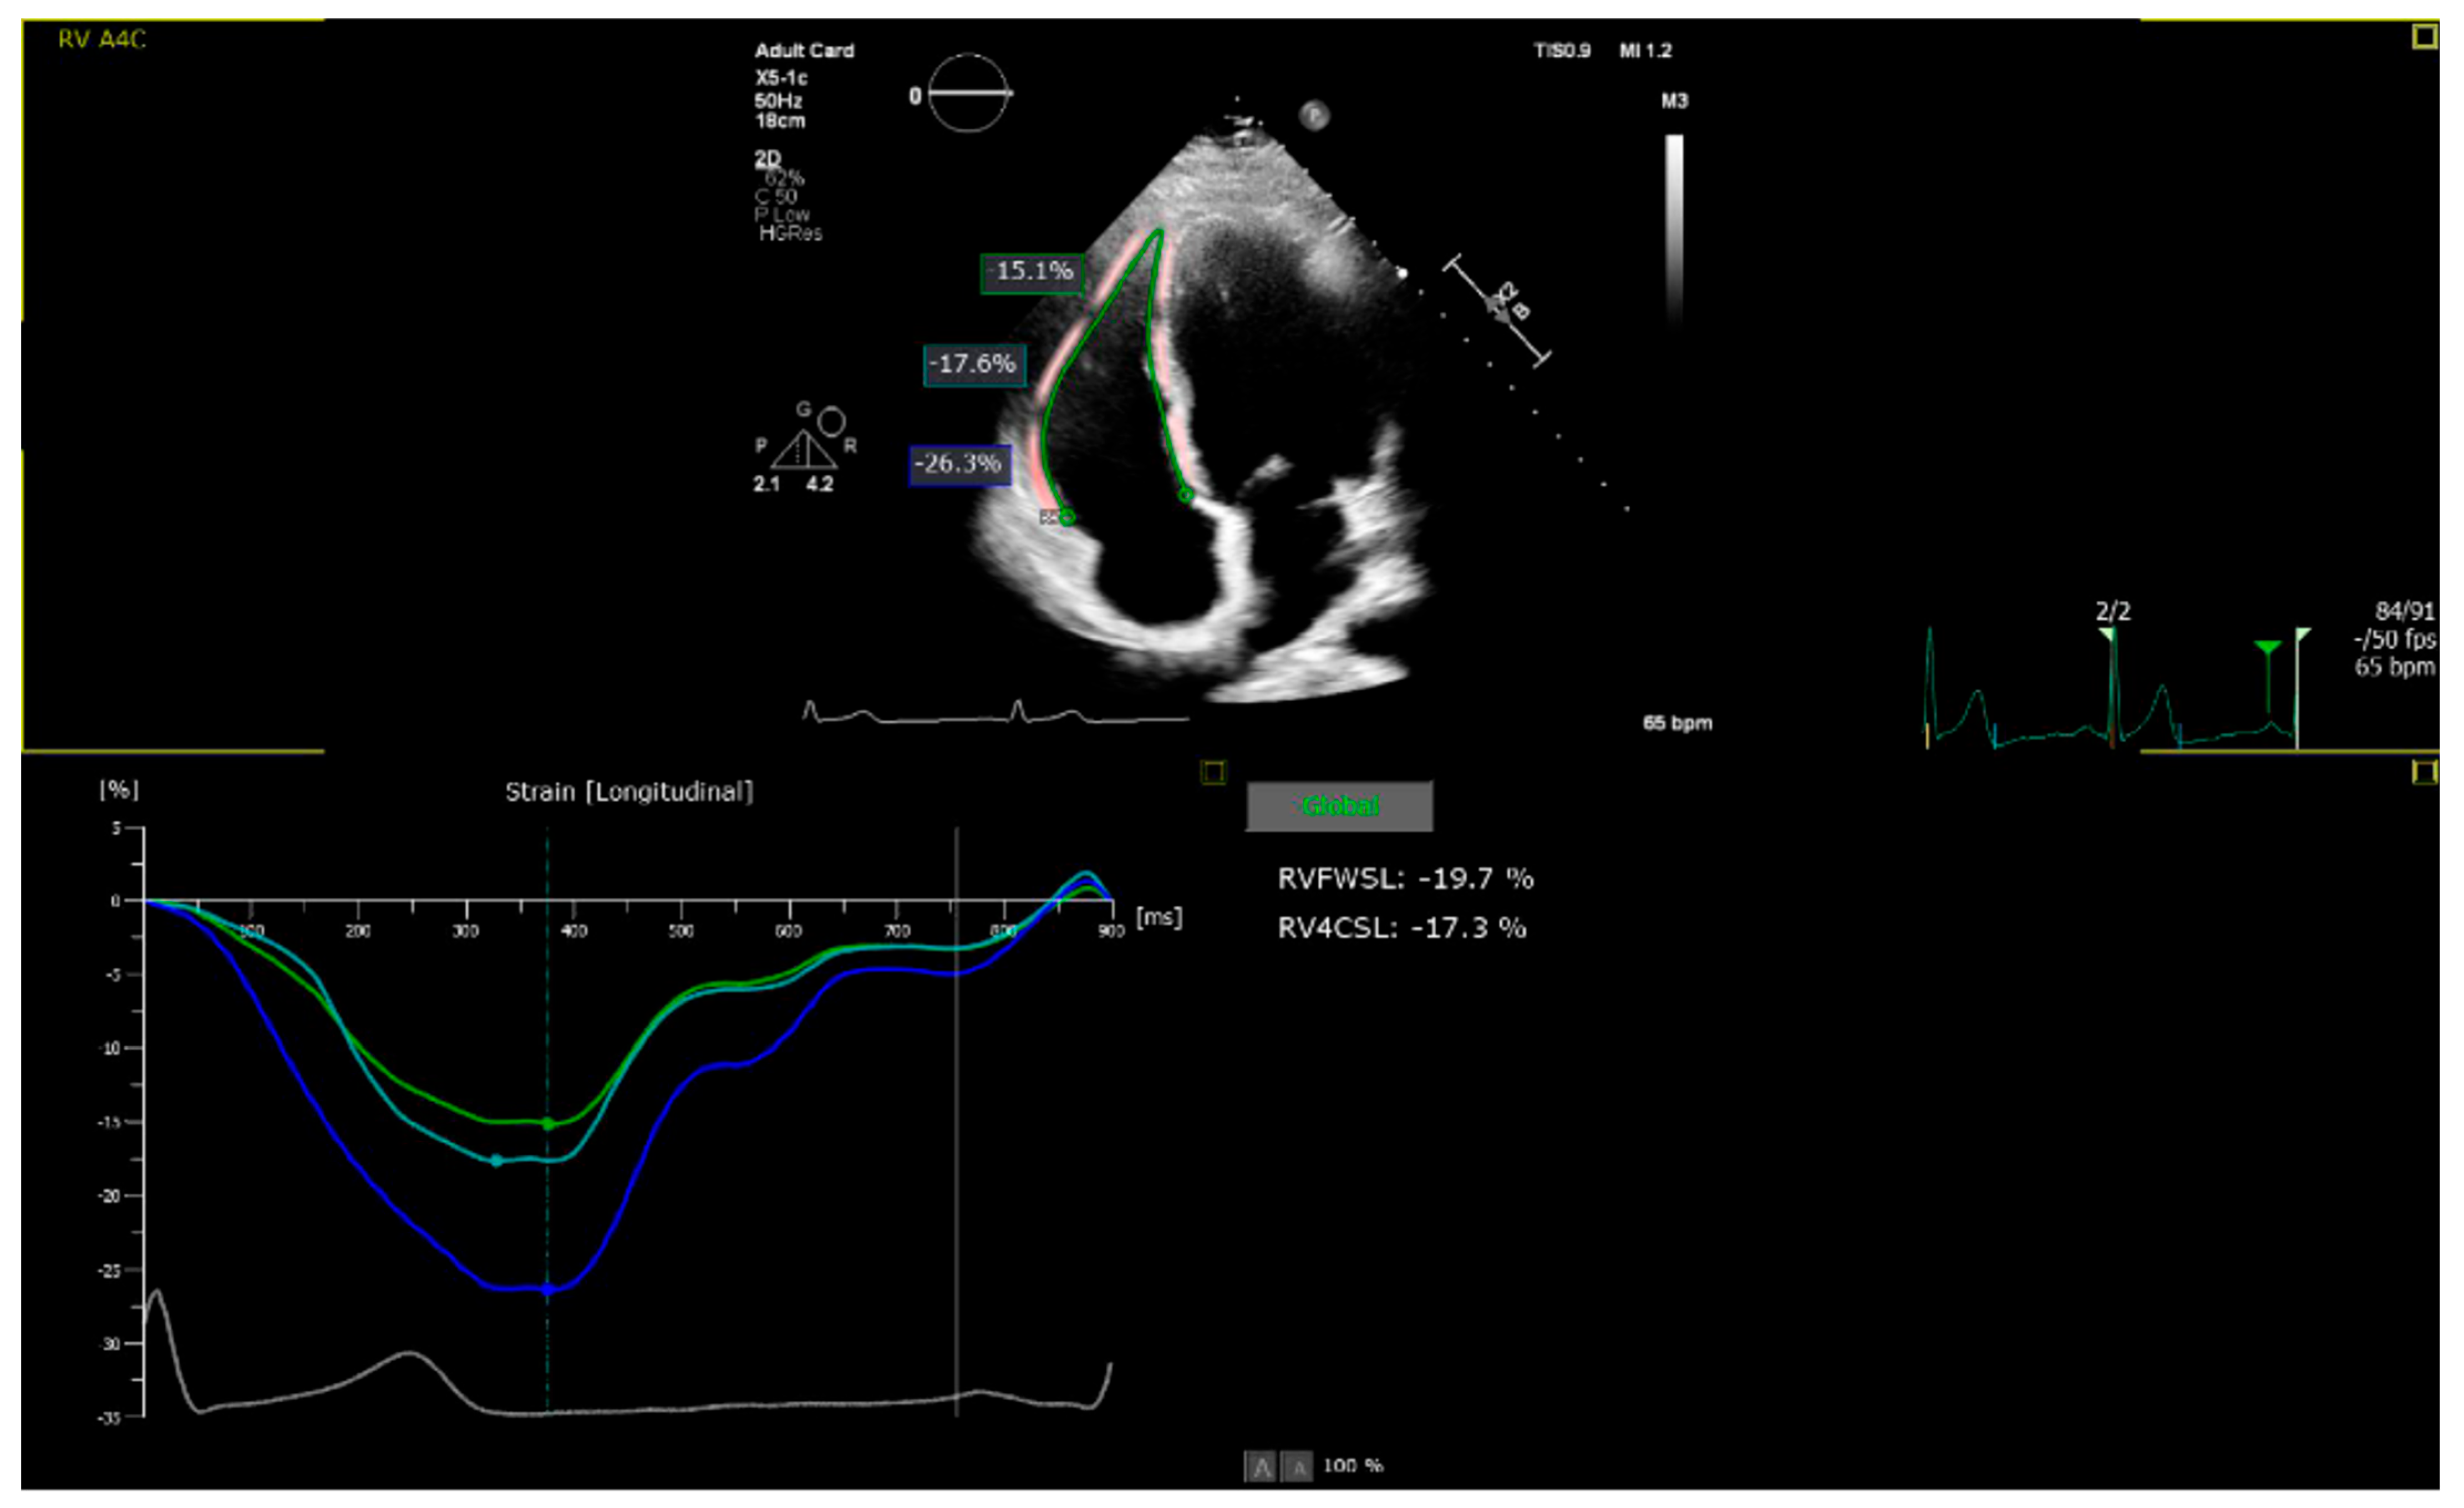

2.2. Echocardiographic Assessment

| 2D RVFWLS (%) | 20.8 ± 5.2 | 27.6 ± 4.0 | 0.32 | p < 0.001 |

| 2D RV4CLS (%) | 18.2 ± 3.8 | 23.3 ± 3.6 | 0.29 | p < 0.001 |